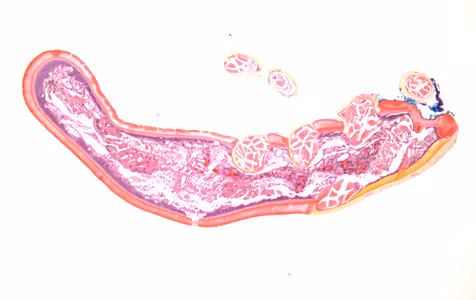

A skin biopsy specimen was collected from the clavicle region of a 45-year-old male who presented with what appeared to be a pigmented lesion. The patient resides in Kentucky and has no known international travel. The biopsy specimen was sent to Pathology for routine histologic work-up. Objects suggestive of an organism were examined on slides stained with hematoxylin-and-eosin (H&E). The attending pathologist captured images and sent them to CDC-DPDx for diagnostic assistance. Figures A–E represent five of the images received. What is your diagnosis? Based on what criteria?

Figure A